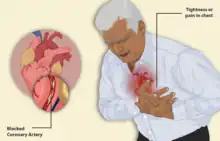

| Illustration depicting angina | |

Angina, also known as angina pectoris, is chest pain or pressure, usually caused by insufficient blood flow to the heart muscle (myocardium).[2] It is most commonly a symptom of coronary artery disease.[2]

Angina pectoris can be quite painful, but many patients with angina complain of chest discomfort rather than actual pain: the discomfort is usually described as a pressure, heaviness, tightness, squeezing, burning, or choking sensation. Apart from chest discomfort, anginal pains may also be experienced in the epigastrium (upper central abdomen), back, neck area, jaw, or shoulders. This is explained by the concept of referred pain and is because the spinal level that receives visceral sensation from the heart simultaneously receives cutaneous sensation from parts of the skin specified by that spinal nerve's dermatome, without an ability to discriminate the two. Typical locations for referred pain are arms (often inner left arm), shoulders, and neck into the jaw. Angina is typically precipitated by exertion or emotional stress. It is exacerbated by having a full stomach and by cold temperatures. Pain may be accompanied by breathlessness, sweating, and nausea in some cases. In this case, the pulse rate and the blood pressure increases. Chest pain lasting only a few seconds is normally not angina (such as precordial catch syndrome).